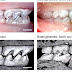

Growing teeth is a bioengineering technology with the ultimate goal to create / re-create new full-molars in a person or an animal.

- Outer - the tooth is grown separately and implanted in the patient.

- Inner - the tooth is grown directly into the patient's mouth.